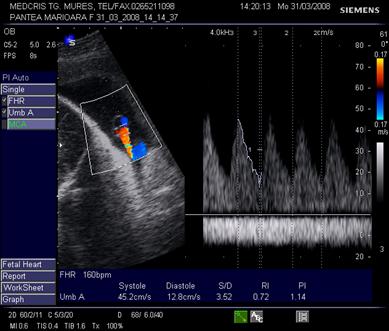

Doppler pe artera ombilicala

Daca fasciculul Doppler ("poarta") este bine centrat, sunetul este optim si spectrul este caracteristic pentru artera din cordonul ombilical. Linia de baza trebuie sa separe fluxul arterial de cel venos.

Derularea benzii cu spectrul Doppler va "curge" pana cand exista parametrii de calitate:

sunet caracteristic

minim 5 cicli consecutivi, identici, bine conturati, deasupra liniei de baza

fluxul venos continuu este sub linia de baza

Fig. nr.321. Spectru Doppler normal pe artera ombilicala